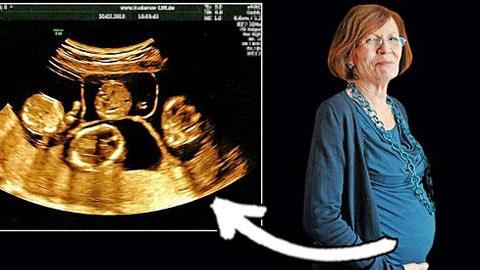

Το να αποκτήσει κανείς τετράδυμα με φυσικό τρόπο είναι εξαιρετικά σπάνιο φαινόμενο! Συγκεκριμένα συμβαίνει 1 φορά στις 700.000!